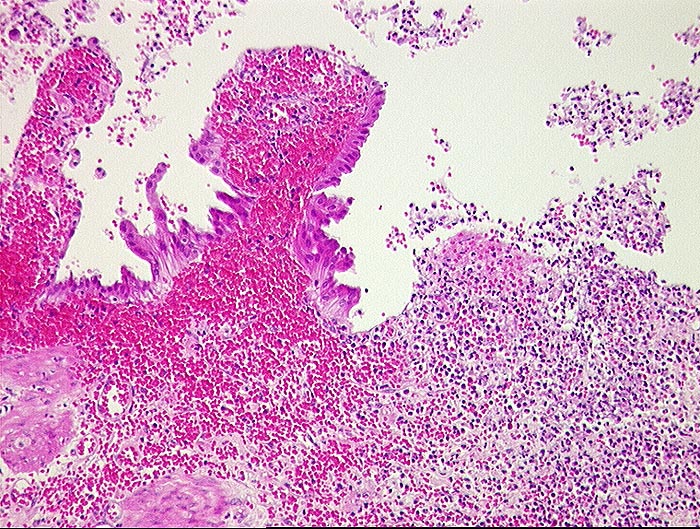

PathoPic ID 493 - Hämorrhagische akute Cholezystitis

Hämorrhagische akute Cholezystitis

Entzündung / Reparatur

Gallenblase

Leber, Gallenwege, Pankreas

Ulzerierte Gallenblasenschleimhaut mit frischen Einblutungen in der Lamina propria.

Akute Cholezystitis.

Histologie